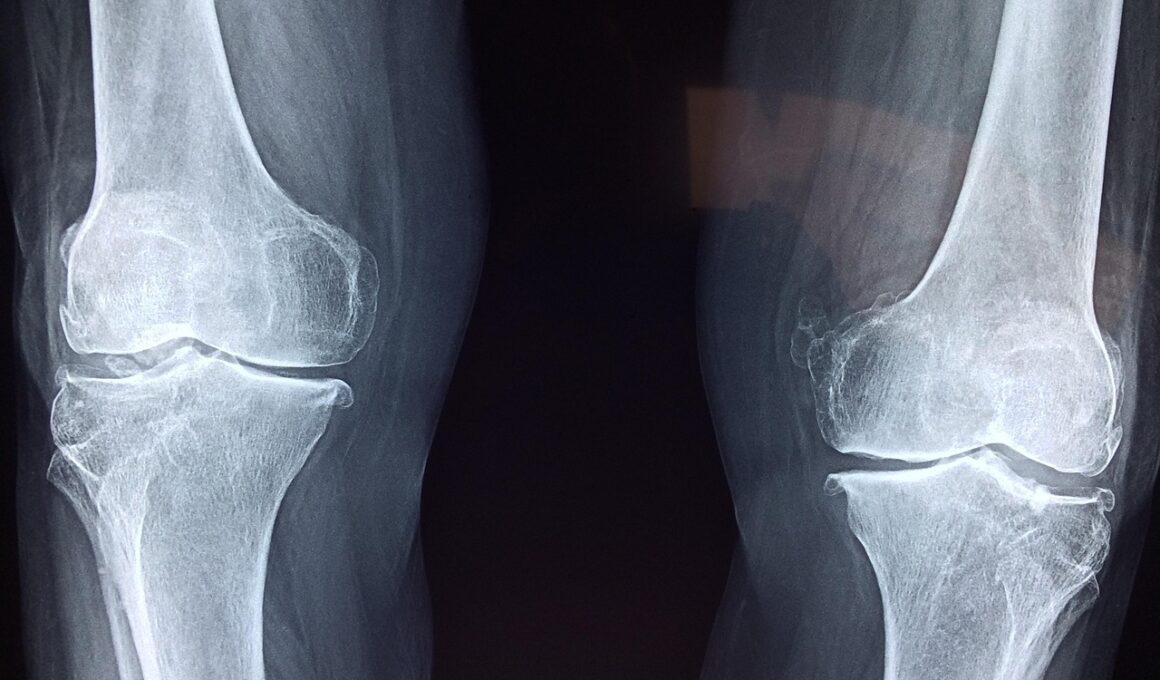

Vegetarian Supplement Strategies to Prevent Joint Degeneration

Joint health is crucial for maintaining an active lifestyle, especially in those following a vegetarian or vegan diet. The right supplements can make a significant difference in joint function and overall physical well-being. Vegetarians and vegans should focus on key nutrients known to support joint health, including omega-3 fatty acids, vitamin D, calcium, and antioxidants. Incorporating a variety of plant-based foods rich in these nutrients is essential. Foods like chia seeds, walnuts, and flaxseeds are excellent sources of omega-3s. Furthermore, fortified plant milks can provide adequate calcium and vitamin D. Regularly consuming these foods may help reduce inflammation, a major factor in joint degeneration. Additionally, individuals should consider speaking with a healthcare provider to tailor a supplement regimen that suits their specific needs. It’s important to ensure that any supplements used are vegan-friendly and free from animal products. With the right approach, vegetarians and vegans can effectively mitigate joint issues through dietary and supplementary means, promoting longevity and mobility throughout their fitness journey.

Regular health check-ups are essential for monitoring joint health, especially for those on vegetarian or vegan diets. Visiting a healthcare professional can help assess nutrient deficiencies and ascertain necessary dietary or supplementary adjustments. Blood tests can determine levels of essential nutrients like vitamin D, calcium, and omega-3 fatty acids, which play vital roles in joint health. Ensuring a sufficient intake of these essential nutrients will help prevent problems commonly associated with joint degeneration. Moreover, discussing joint pain concerns with a healthcare provider can lead to early intervention strategies, which can be advantageous. For individuals engaging in rigorous physical activities, having a physical therapist can also provide insights into proper workout techniques that support joint health. Listening to the body’s signs, such as persistent pain or limited mobility, is critical and should not be ignored. Regular check-ups and consultations with health professionals can contribute to a comprehensive approach in effectively managing joint health over time, allowing for a proactive stance against degeneration and enhancing the quality of life.